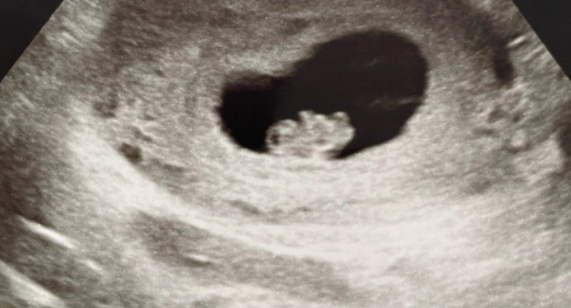

임신이 이렇게 매 순간 걱정되고, 또 아이가 태어난 이후까지도 준비해야 할 게 많다는 걸 그때 처음 알았죠.

임신이라는 건 축복이지만, 예상치 못한 변수들도 함께 따라오죠.

선천성 심장질환, 미숙아 치료비, 조산 등 태어날 때부터 병원 신세를 져야 하는 아이들도 있고,

그리고 중요한 건, 출생 직후부터 바로 보장을 받기 위해선 반드시 임신 중에 가입해야 한다는 점이에요.